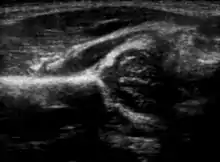

α and β angles used in hip ultrasound

Hip dysplasia can be diagnosed by ultrasound[42] and projectional radiography ("X-ray").[43] Ultrasound imaging is generally preferred at up to 4 months due to limited ossification of the femoral head up until then, and is the most accurate method for imaging of the hip during the first few months after birth. However, in most instances, ultrasound screening should not be performed before 3 to 4 weeks of age because of the normal physiologic laxity.[44][notes 1] When universal with targeted ultrasound screening was compared, the former results in an insignificant reduction in the late diagnosis of hip dysplasia, which is why universal ultrasonographic screening of newborn infants is not recommended by the American Academy of Pediatrics.[11]